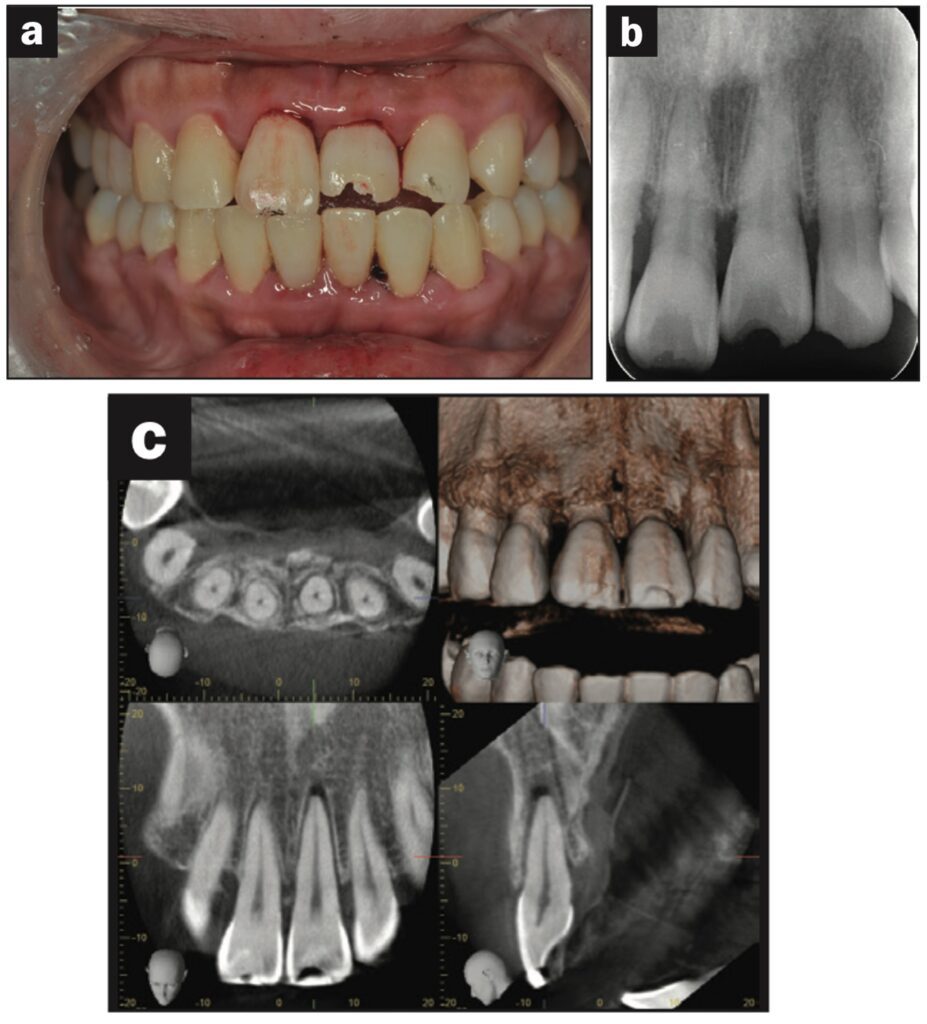

Bệnh nhân nữ 42 tuổi bị ngã khiến răng cửa giữa hàm trên bên trái bị lệch về phía vòm miệng. Đường gãy xương ổ răng ở phía khẩu cái được thấy trên CBCT.

Răng được nắn chỉnh và cố định bằng composite quang trùng hợp rồi lấy dấu. Hai tiếng sau, bệnh nhân quay lại và nhận khay duy trì. Bệnh nhân được hướng dẫn đeo khay duy trì cả ngày trừ khi đánh răng.

Các thử nghiệm tủy được thực hiện sau 7 và 28 ngày. Đánh giá độ lung lay răng, gõ và sờ, thử tủy EPT và chụp X quang được thực hiện sau 28 ngày.

Sau 28 ngày theo dõi, răng hơi lung lay và không đáp ứng với thử tủy EPT. Sau 2 tháng theo dõi, răng không bị đổi màu, không lung lay, âm tính với EPT và hơi nhạy cảm khi gõ. Không có tổn thương quanh chóp trên X quang và không có lỗ dò. Sau 3 tháng theo dõi, răng đã đáp ứng với EPT (9/10) và có cảm giác đau nhẹ khi gõ.

Sau 4 tháng theo dõi, răng đã phản ứng với EPT (9/10) và không còn nhạy cảm với gõ.